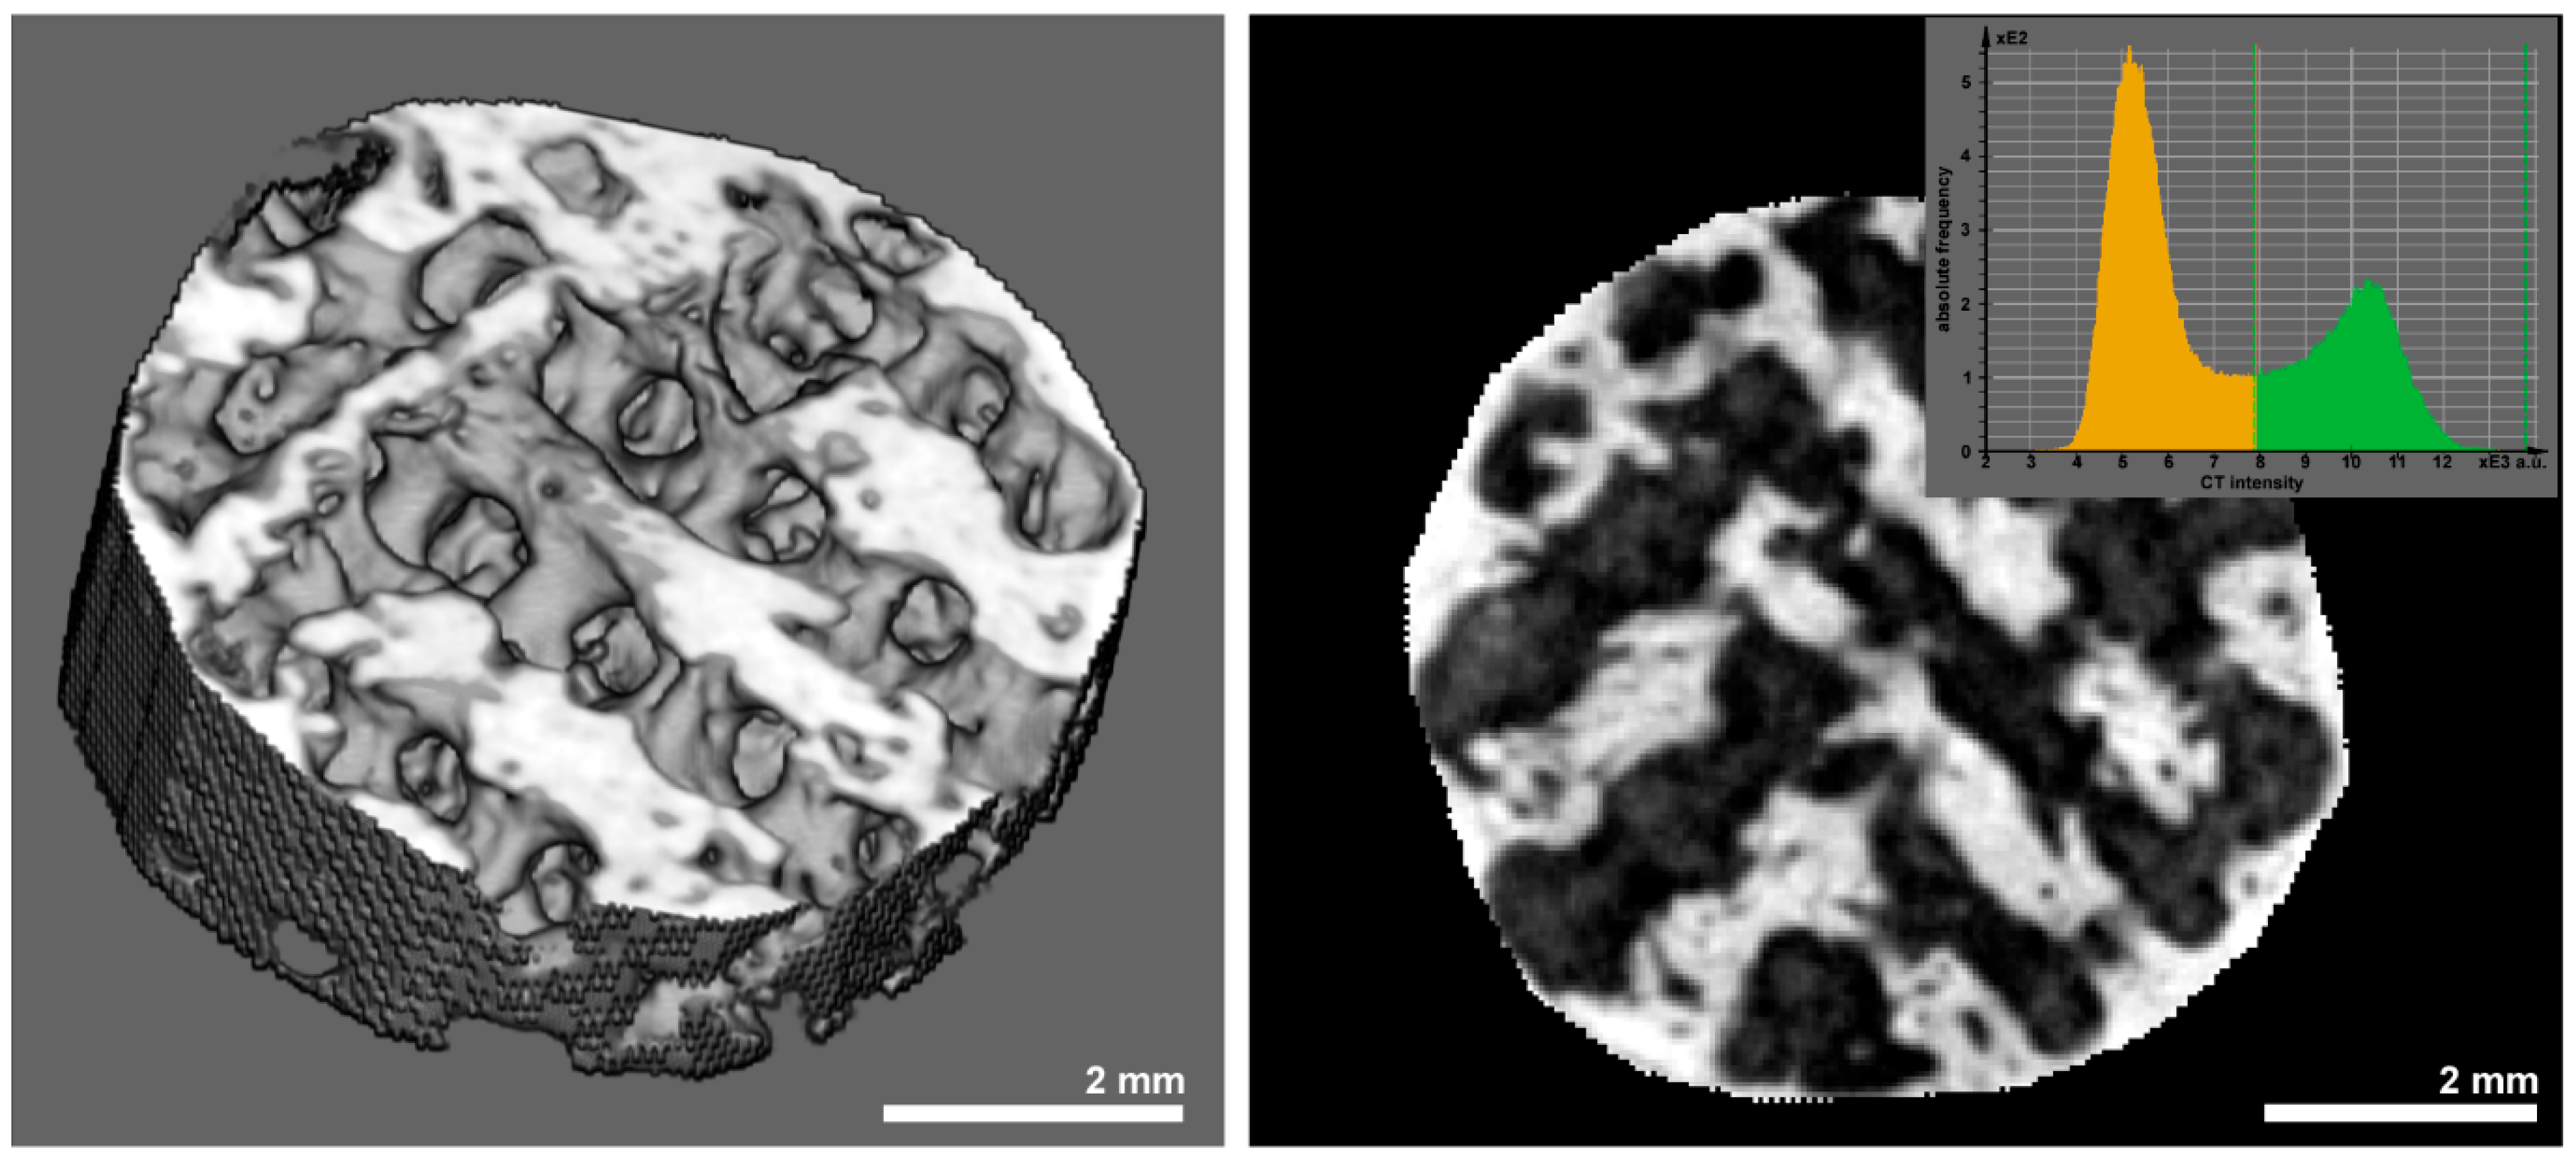

3.3. Histomorphometry and Μct